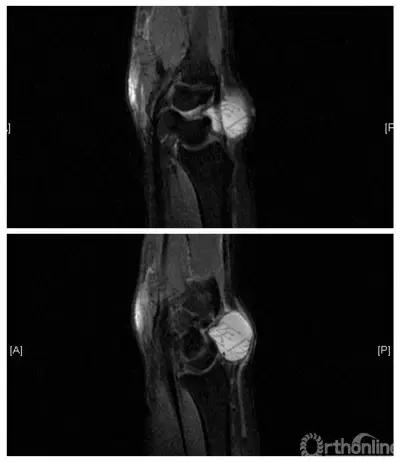

典型病例(腕背腱鞘囊肿)

女,27岁,病史3年,保守治疗后复发。

穿刺抽液及中医针刺治疗后留下难看疤痕并3个月后复发。

行腕关节镜手术,术中可见囊肿蒂及切除后显露出腕背伸肌腱。